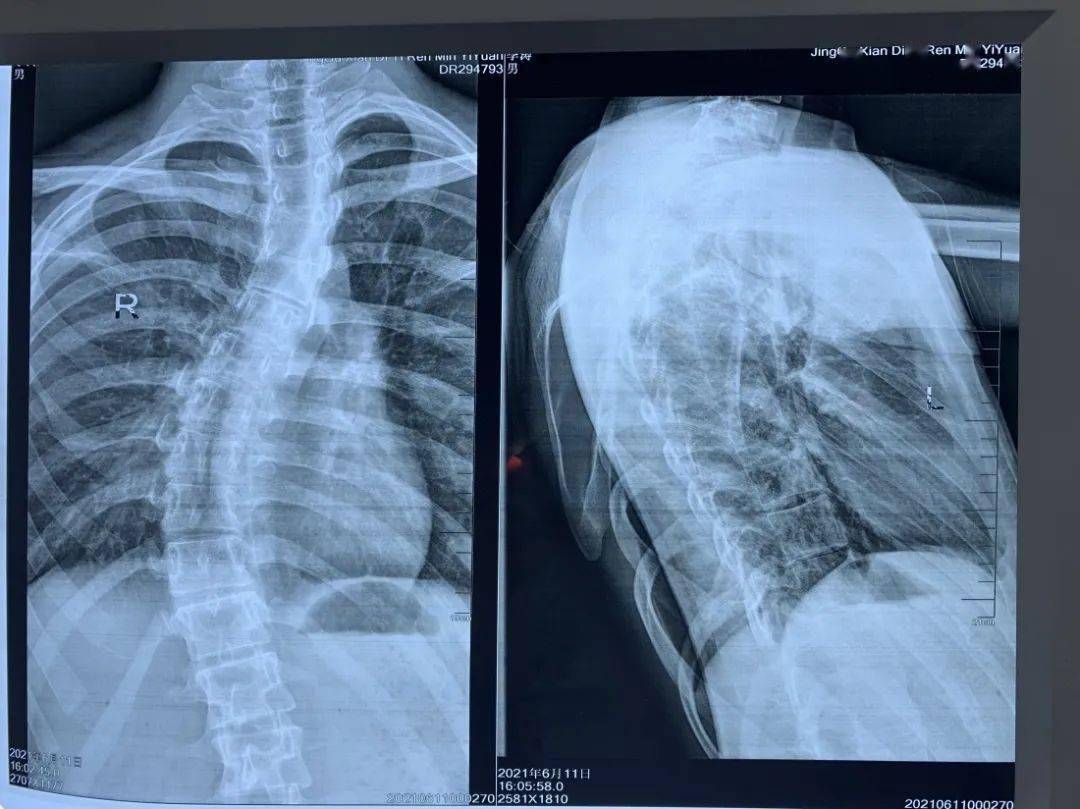

腰椎管狭窄症并脊柱侧弯的治疗前后比较 - 好大夫在线

术后正侧位片选择性融合胸弯,保留腰椎活动度,术后矫形效果满意,内